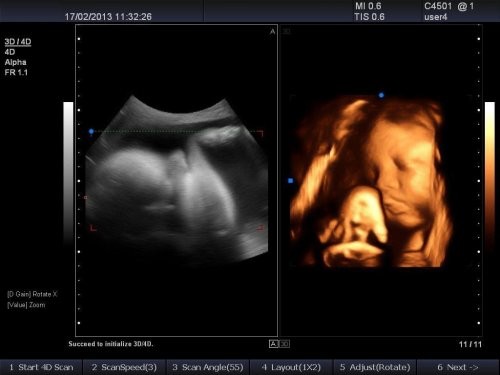

四维彩超做的是结构排查,比如说心肝脾肺肾大脑的结构、脑室的宽度、嘴唇完整性等等,这些结构在22-26周之间能在超声下较为清晰地显示,所有孕妇在做超声前都被告知超声并非能够排查出所有的异常,仅仅是大结构的筛查。至于耳孔、睁眼闭眼、微小的尾椎开裂排畸彩超根本无能为力。

四维彩超示例